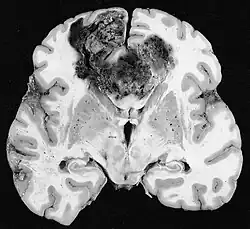

Vascular mimicry was first discovered in 1999 by Maniotis et al. who identified blood supplying channels in malignant melanoma that were composed entirely of tumor cell based structures. They found that cancer cells had taken on endothelial cell properties and were forming blood conducting vessels independent of normal angiogenesis pathways.[2] This finding spurred interest within the research community to discover the cause of this pathway and its relevance to disease.

Clinically, VM is diagnosed through immunohistochemistry (IHC) and Periodic acid-Schiff stain (PAS) of patient tumor biopsy. IHC staining identifies the expression of common biomarkers of endothelial cells such as CD31, while PAS staining marks the extracellular matrix for glycoproteins, laminin, proteoglycans, heparin sulfate and collagens, which are known to be a sign of VM.[2] Clinicians diagnose a tumor as having VM by CD31-/PAS+ expressing blood conducting vessels, indicating that there are no endothelial cells but still vasculature present.[2][3]

Melanoma is an aggressive skin cancer which has been shown to utilize both angiogenesis and vascular mimicry to drive metastasis and also increase treatment resistance.[1] Metastatic melanoma has very poor survival outcomes with a median survival of 6 months.[19] VM has been identified to be present only in metastatic and very aggressive melanomas. Major biomarkers of VM in melanoma include: VEGF-A, HIF-1A, and Nodal.